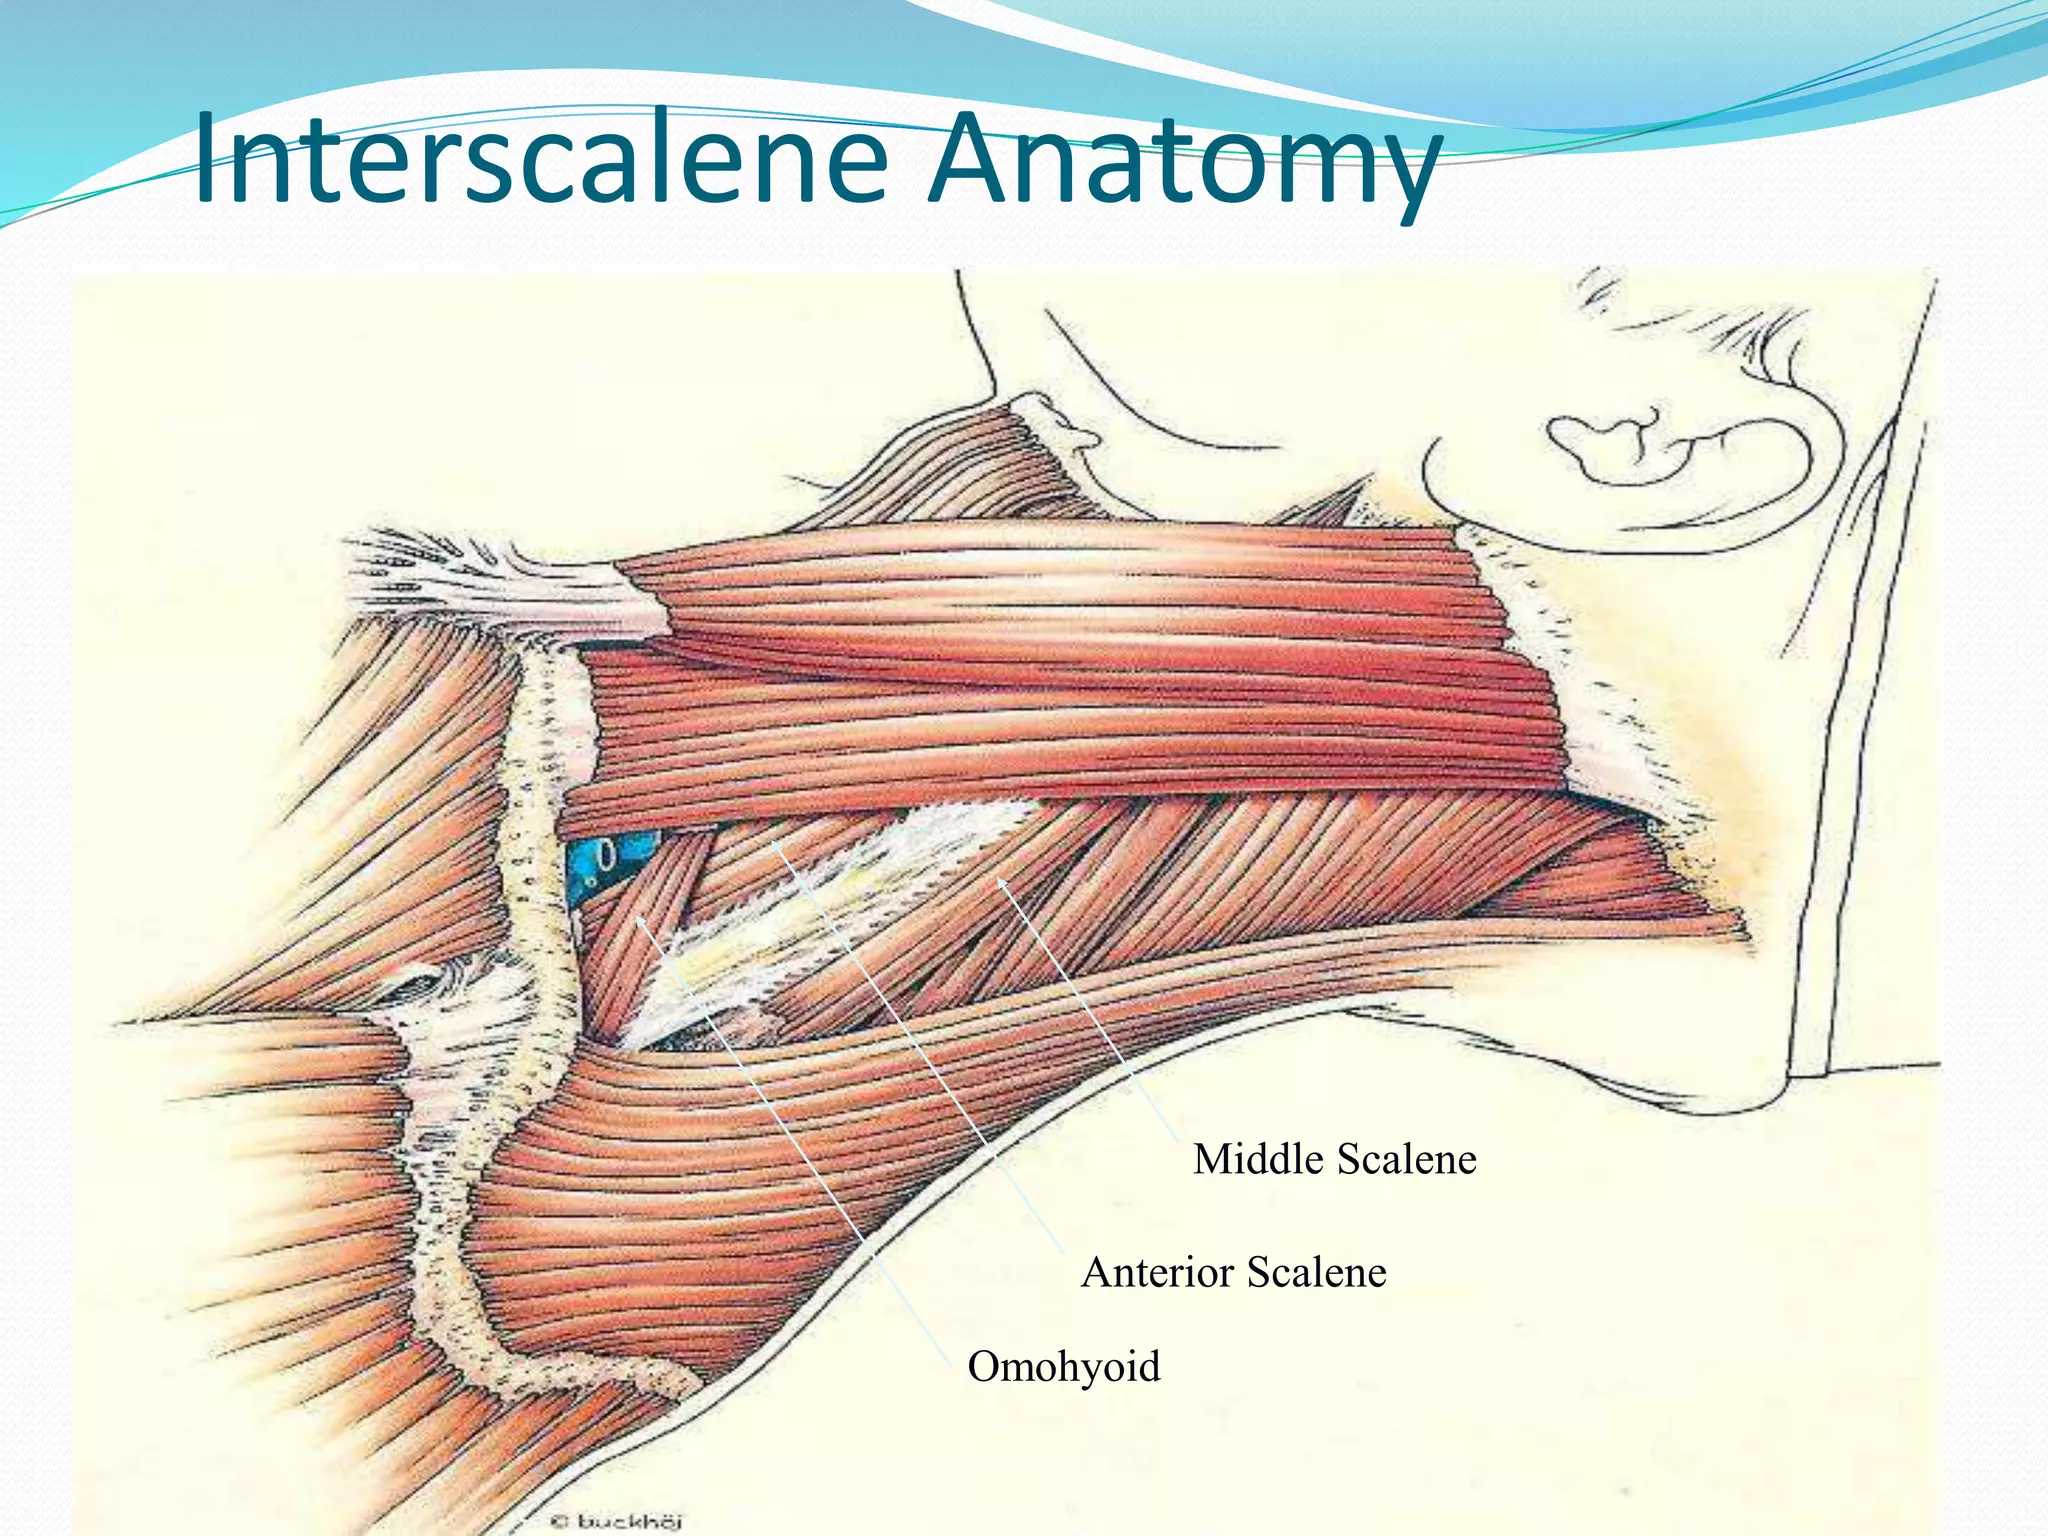

This document provides an overview of brachial plexus anatomy and techniques for brachial plexus nerve blocks. It begins with a description of the brachial plexus formation from cervical and thoracic nerve roots and its branching pattern. Four main approaches for brachial plexus nerve blocks are described: interscalene, supraclavicular, infraclavicular, and axillary. Details are provided on the anatomy and techniques for performing interscalene and supraclavicular brachial plexus blocks. Ultrasound guidance is discussed as an advancement which allows real-time visualization of needle and nerve. Complications are also summarized.